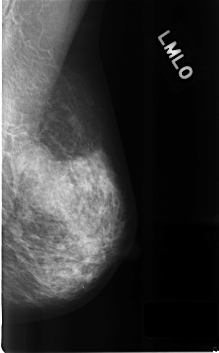

C_0314_1.LEFT_MLO

LEFT_MLO LINES 4584 PIXELS_PER_LINE 2840 BITS_PER_PIXEL 12 RESOLUTION 50 NON_OVERLAY